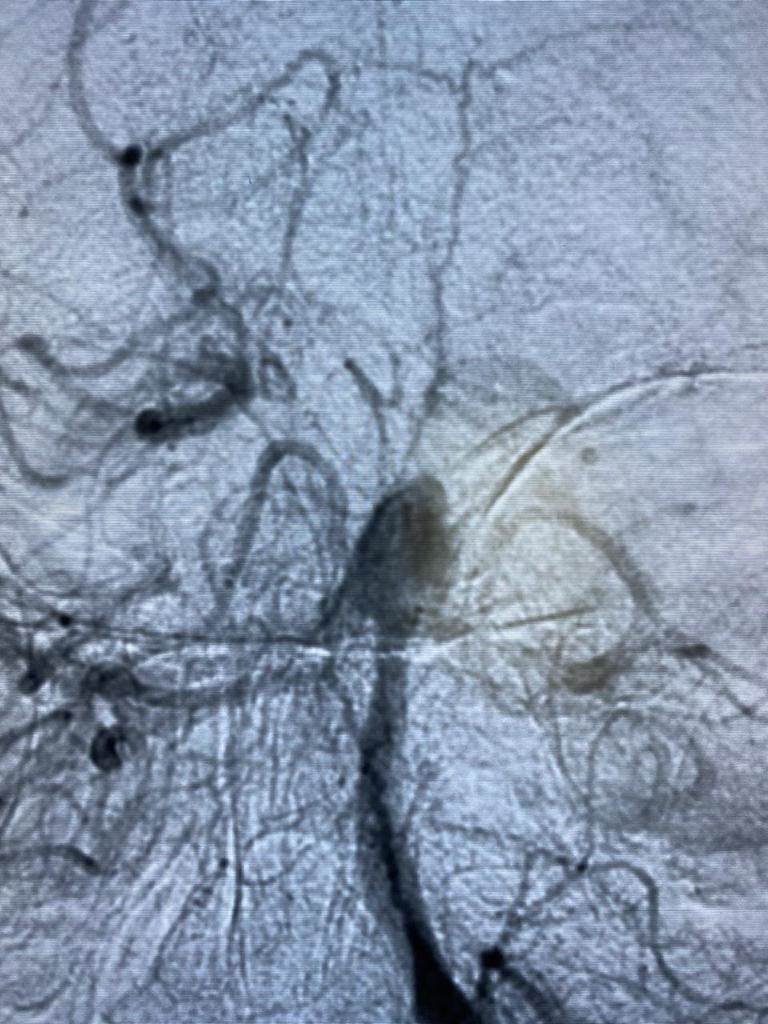

وأضافت الهيئة ،أنه تم عمل الفحوصات الطبية المريضة التي تبلغ من العمر ٥٠ عام فور دخولها مستشفى النصر التخصصي، وتبين أنها تعاني من تمدد شرياني بالشريان القاعدي بالمخ ، وعليه تم إجراء القسطرة التشخيصية المخية للمريضة ووضع الخطة العلاجية لها على يد الأستاذ الدكتور أحمد بسيوني، استشاري القسطرة المخية بمستشفيات هيئة الرعاية الصحية ببورسعيد، وهي الآن تحت الملاحظة وحالتها مستقرة.

وتابع أ.د. أحمد بسيوني أستاذ المخ والأعصاب وقسطرة المخ بطب عين شمس، والمشرف على القسطرة المخية بمستشفيات هيئة الرعاية الصحية ببورسعيد، أن هذا الإجراء يأتي ضمن حزمة من الإجراءات المنوط بها قسم طب المخ والأعصاب بمستشفيات هيئة الرعاية الصحية ببورسعيد برئاسة الاستاذ الدكتور هاني عارف، لافتًا إلى الخدمات العلاجية التي تقدمها وحده السكتة الدماغية وإذابة الجلطات المخيه في زمن قياسي، والذي سيسهم في تقليل معدلات الوفيات والإعاقه للمواطن البورسعيدي، فضلًا عن الاختبارات الفسيولوجية لمرضي المخ والأعصاب، وعلاج مرضي التصلب المتناثر، ومجموعة كبيرة من الخدمات الأخري التي تضمن حصول المواطن البورسعيدي علي الخدمة الأمثل، والتي تضاهي في جودتها أعظم المراكز العالمية وداخل المحافظة دون تحمل مشقة السفر والعناء من أجل توافر الخدمة.